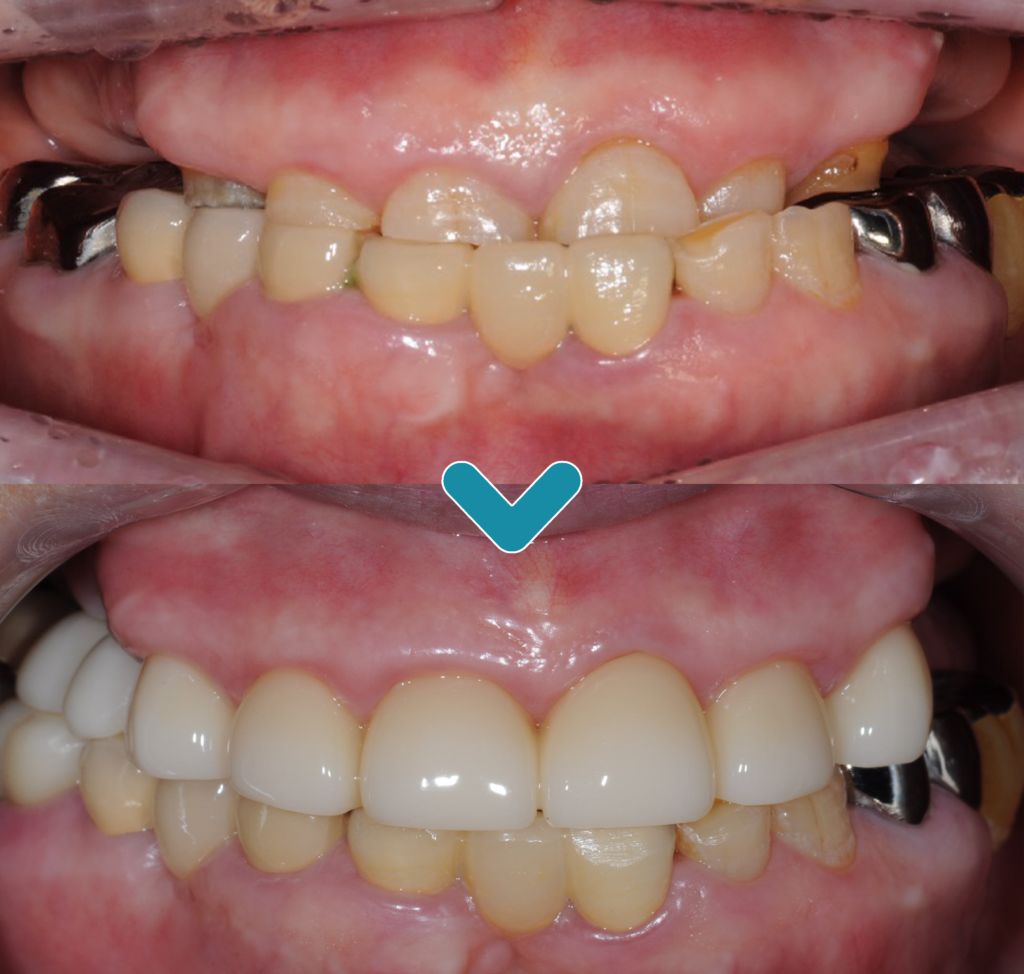

어금니의 임플란트와

앞니 보철치료까지

완료되고 난 후에는 기존 거꾸로

물리고 있었던 교합까지

회복할 수 있었습니다.

다른 사람들과

대화를 하거나 웃을 때에도

치아가 보이는 것을 꺼려 하셨지만

이제는 환하게 웃을 수 있으시다고

하시며 기뻐하셨고 편안한 식사에

만.족도가 높으셨습니다.